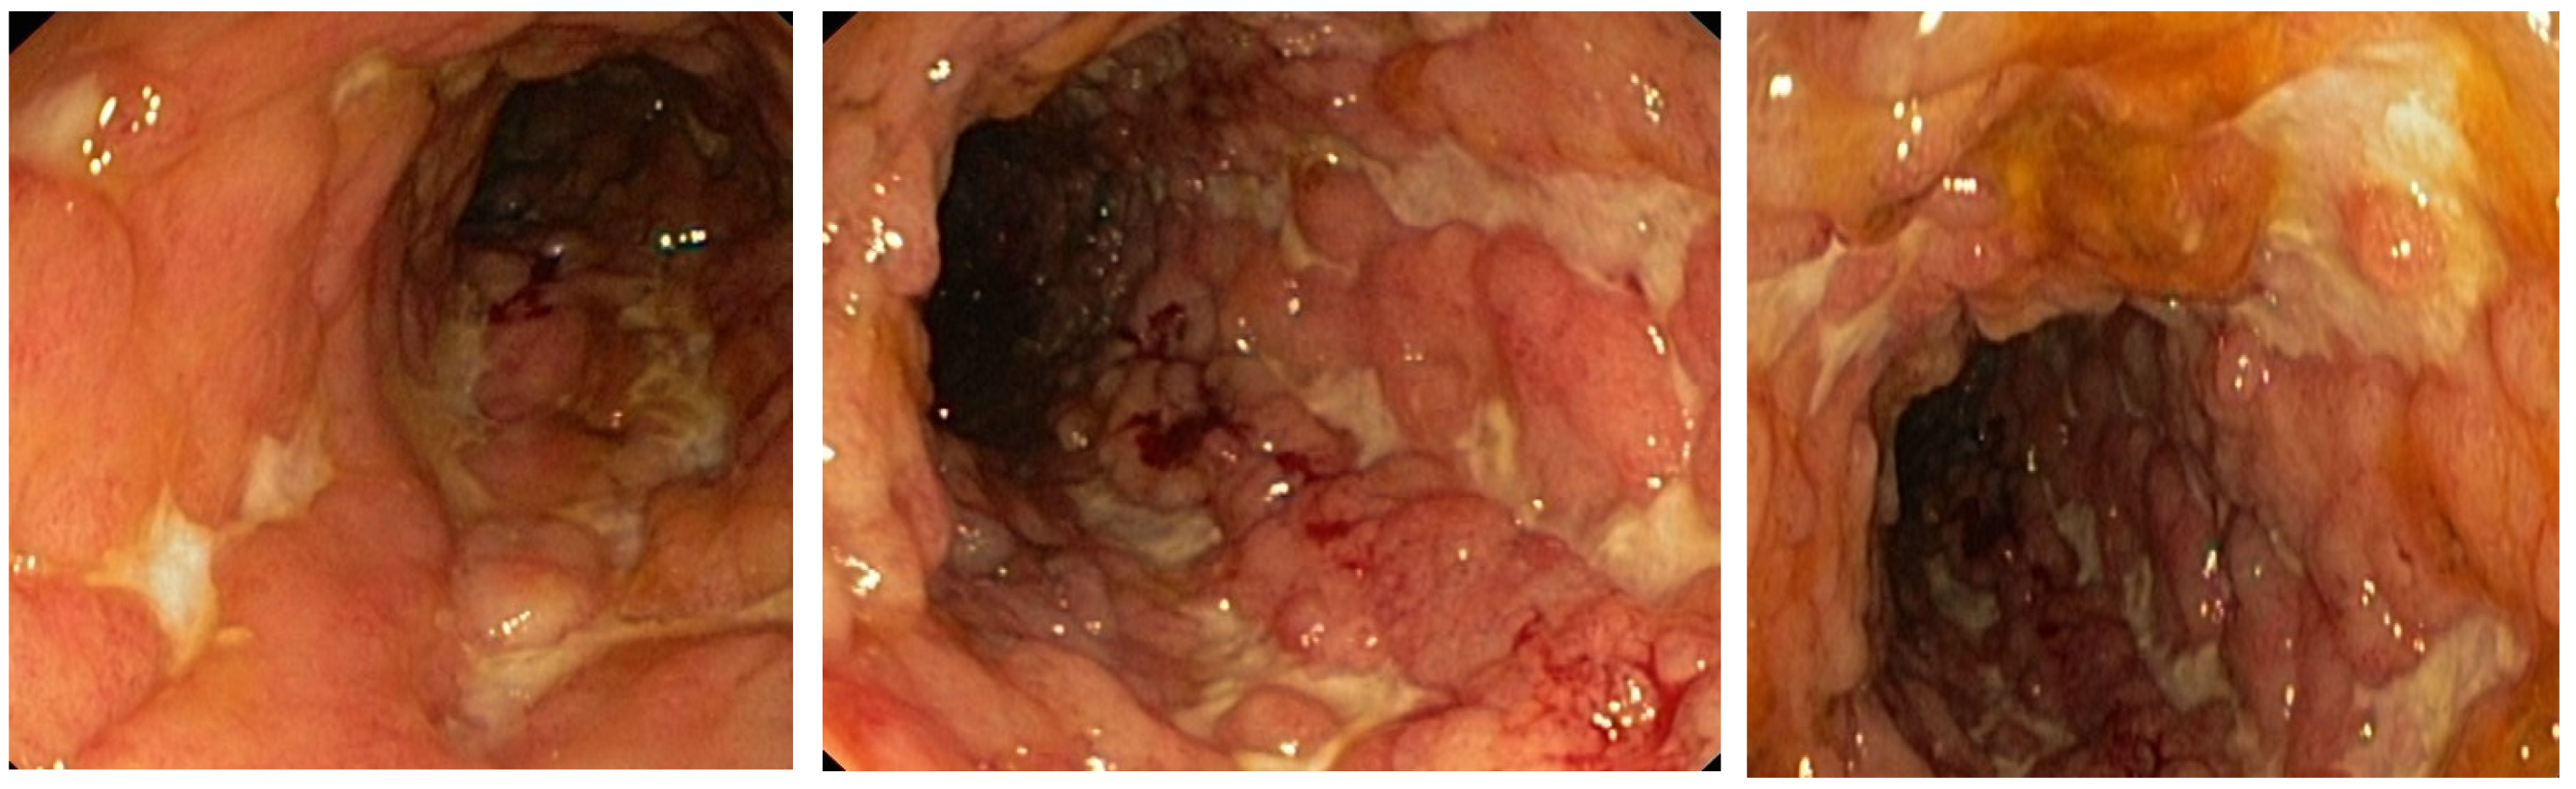

During steroid tapering, at the dose of 35 mg prednisolone, patient had increased number of bowel movements to four–five liquid stools daily followed by increase in CRP levels (141 mg/L) and hemolytic crisis. After detailed workup from an immunologist and hematologist, AIHA was considered as an EIM of CD. In addition, the previous PTE was now considered provoked, since tests for inherited and acquired thrombophilia were negative. Due to steroid-dependent form of disease, we initiated treatment with infliximab in combination with azathioprine. The patient responded to first infliximab infusion, CRP levels decreased (23 mg/L), and she had two formed stools. The patient was discharged and the second induction dose administered after 2 weeks was uneventful. At the third induction dose, on week 6, CD was in clinical remission, with two formed stools daily, no fever, and no abdominal pain, but laboratory signs of another hemolytic crisis were observed with severe anemia (Hgb 60 g/L). We decided to increase the corticosteroid dose to 40 mg prednisolone and blood was taken to determine infliximab trough level and antibodies. Infliximab trough levels were low (0.73 mg/mL) with negative antibodies, so we optimized the treatment regimen by shortening the interval to 4 weeks. The patient responded well, steroids were weaned, and the patient was in clinical and laboratory remission from February 2017 until July 2019. A control colonoscopy in December 2018 confirmed endoscopic remission and low histological activity, as seen in Figure 2. In July 2019, the patient experienced a relapse of CD with abdominal pain and up to 10 liquid bloody stools daily. Infliximab trough levels were low (0.5 mcg/mL) with elevated antibodies (46 IU/mL). The patient was admitted to the Clinic for gastroenterology and hepatology, University Clinical center of Serbia, and started on steroids. The biologic drug was changed within class to adalimumab, as the patient was stable on the first anti-TNF for more than 2 years. Unfortunately, this resulted in a merely partial clinical response with no clinical remission. In October 2019, a colonoscopy revealed severely active disease from the rectum to hepatic flexure, and the biological drug was changed from one of the anti-TNF class to vedolizumab. The patient has since been in clinical, laboratory and endoscopic remission with no more flairs of AIHA. The colonoscopy performed in November 2020 showed endoscopic remission of the disease. Pathohistology confirmed remission with only focal inflammation of low activity. The patient got pregnant, and the pregnancy was uneventful. In July 2021, an elective Caesarian section was performed, and she delivered a male baby (birth weight 4400 g, APGAR score 9). Vedolizumab therapy is ongoing, and the patient is still in remission.

Figure 2. Colon mucosa appearance on colonoscopy performed in December 2018. Note the absence of active Crohn’s disease.